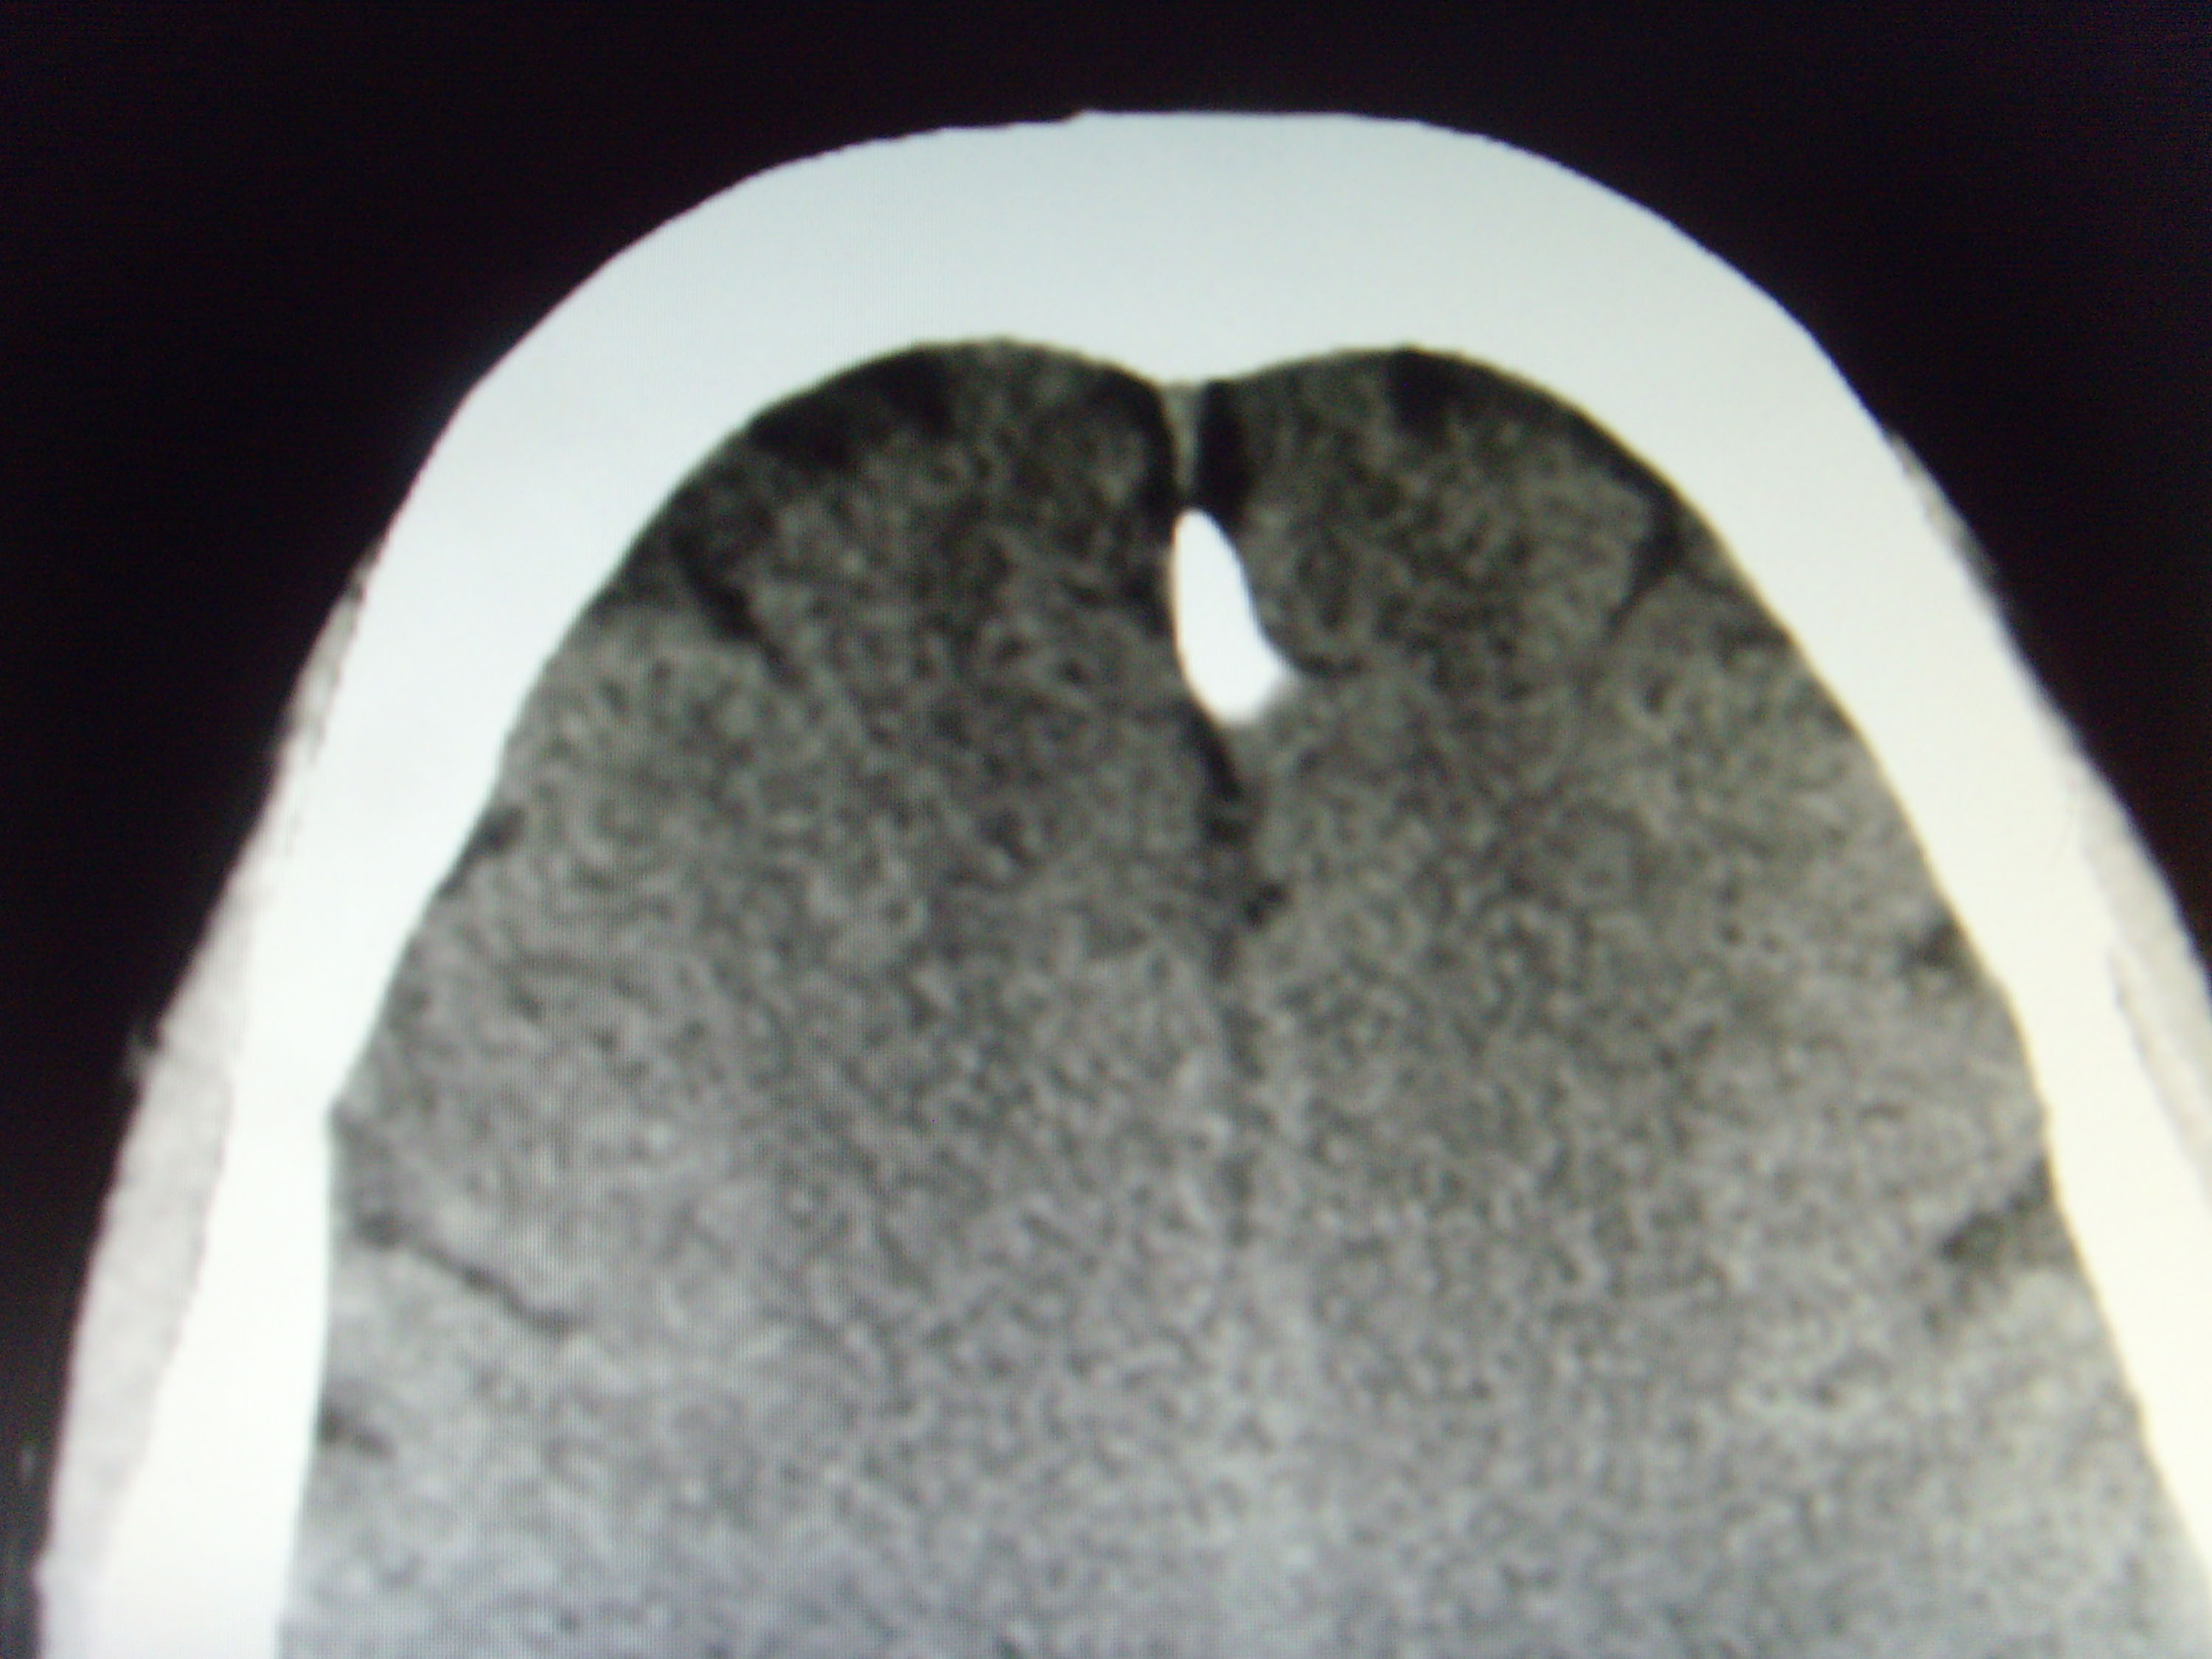

CT52282:大脑镰旁高密度诊断什么?

本帖最后由 cefcmj 于 2016-10-14 17:45 编辑 男,53岁,头晕,头痛1年,大脑镰旁高密度诊断什么?

大脑镰钙化或骨化。

钙化

与脑膜瘤如何鉴别?